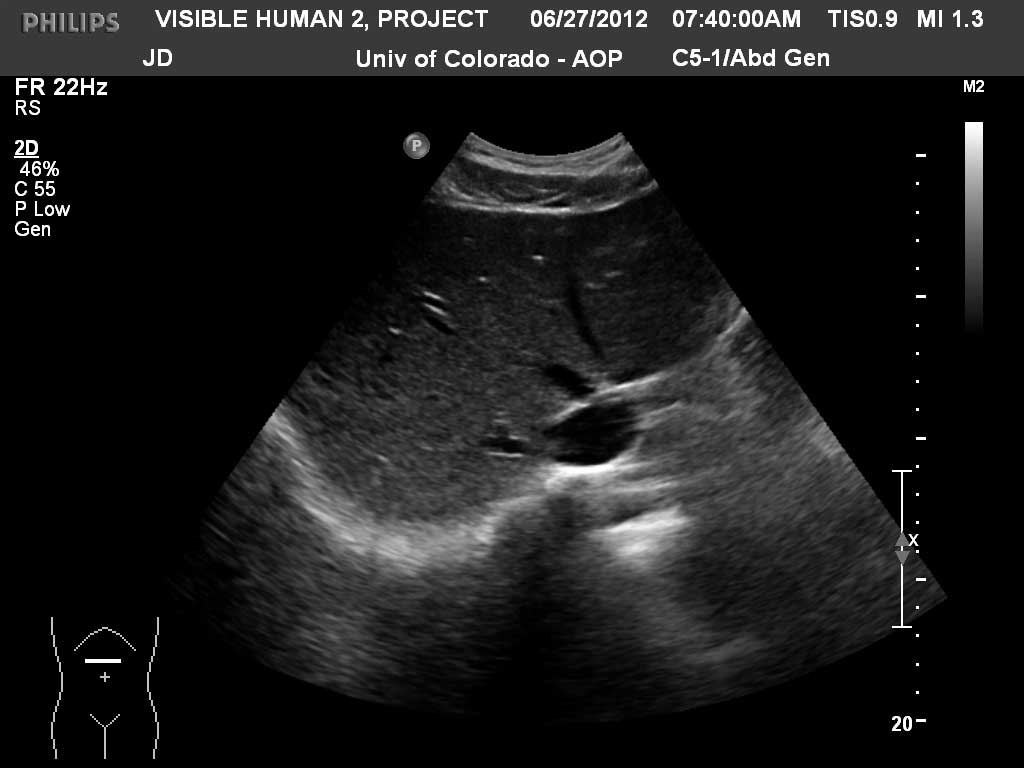

Transverse Liver

Diaphragm

Liver

Inferior Vena Cava

Left Hepatic Vein

Middle Hepatic Vein

Right Hepatic Vein